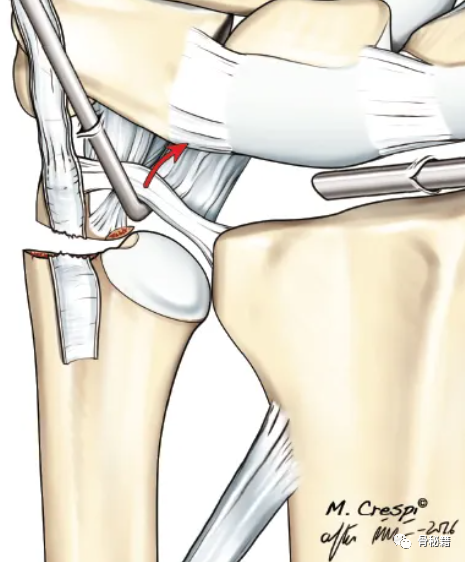

采用茎突入路进行手术复位与固定

拧入空心螺钉

固定后 术中用探钩检查TFCC稳定性,发现固定后稳定性较好